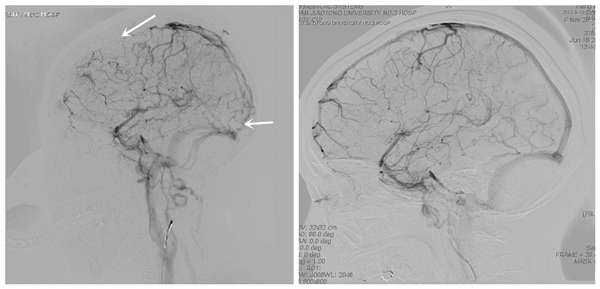

术前造影 术后造影

2015年许刚、崔刚两位医师在广泛阅读国内外文献并与国内该领域的权威专家进行深入交流后申请了《Solitaire-AB支架机械取栓联合溶栓治疗颅内静脉窦血栓》的新技术新疗法,同年底他们成功为一位重危CVST患者完成了西北首例机械取栓联合溶栓治疗,取得了非常满意的效果。截止目前共完成5例重危CVST患者的机械取栓联合溶栓治疗,均取得满意疗效,无1例产生任何手术并发症。其中1例患者因效果满意,陕西传媒网进行了专题报道。近期两位医师受邀分别在唐都医院、西京医院及西北脑血管病论坛进行了专题交流,取得了较大反响,扩大了我院在治疗CVST方面的影响,取得了良好的社会效果,同时也标志着我院在CVST治疗领域,迈开了重要的一步。